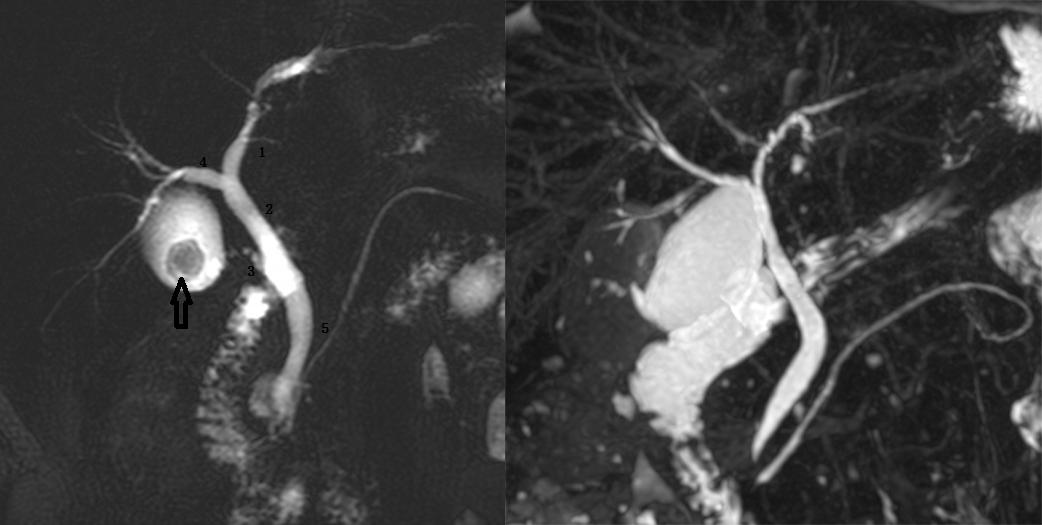

Ⅰ型:肝左右管汇合肝总管,胆囊管与肝总管汇合胆总管。左图:1 为肝左管,2 为肝总管,3 为胆囊管,4 为肝右管,5 为胆总管。黑箭头为胆囊结石。

图为胆总管结石继发梗阻患者。Ⅱ型:肝右前、右后肝管与肝左管汇合肝总管,呈三叉状,1 为肝右前肝管,2 为右后肝管,3 为肝左管,4 为肝总管,箭头为肝总管及胆总管结石。